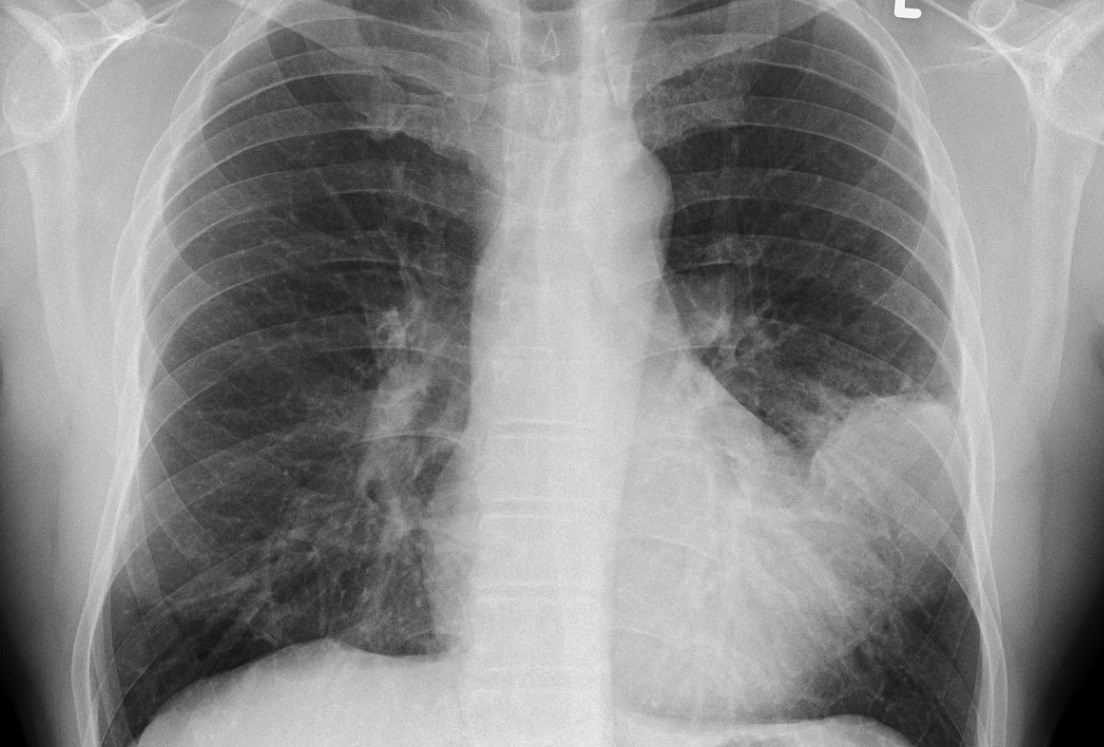

Karşılaştırılan röntgen sonuçları büyük dikkat çekti. En soldaki görselde sigara içen bir bireyin akciğer filmi görülürken sağdaki filmde ise Kovid-19’u yenmiş bir bireyinki bulunuyor.

Akciğer filminde siyah alanlar ne kadar fazla ise o kişinin ciğer kapasitesi ve sağlığı o kadar iyi demektir. Beyaz kısımların artması ise akciğerin kapasitesinin azaldığı anlamını taşır.

Karşılaştırılan röntgen sonuçlarıyla Kovid-19’u geçirmiş ve sağlığına kavuşmuş kişilerin ciğerlerinde görülen hasarın sigara bağımlısı olan kişilerden çok daha kötü olduğunu gözler önüne seren Bankhead-Kendall, ‘Sağlıklı bir bireyin röntgen sonucunda siyah alan büyük olur. Bu da o kişinin ciğerlerine alabileceği oksijen seviyesini gösterir.

Sigara içenlerde hafif hareler yer alırken Covid-19 hastalarının ciğerleri ise bembeyazdır. Yani bu da koronavirüsü yenenlerde bile akciğer sorunları yaşanabildiğini gösteriyor’ açıklamasında bulundu.